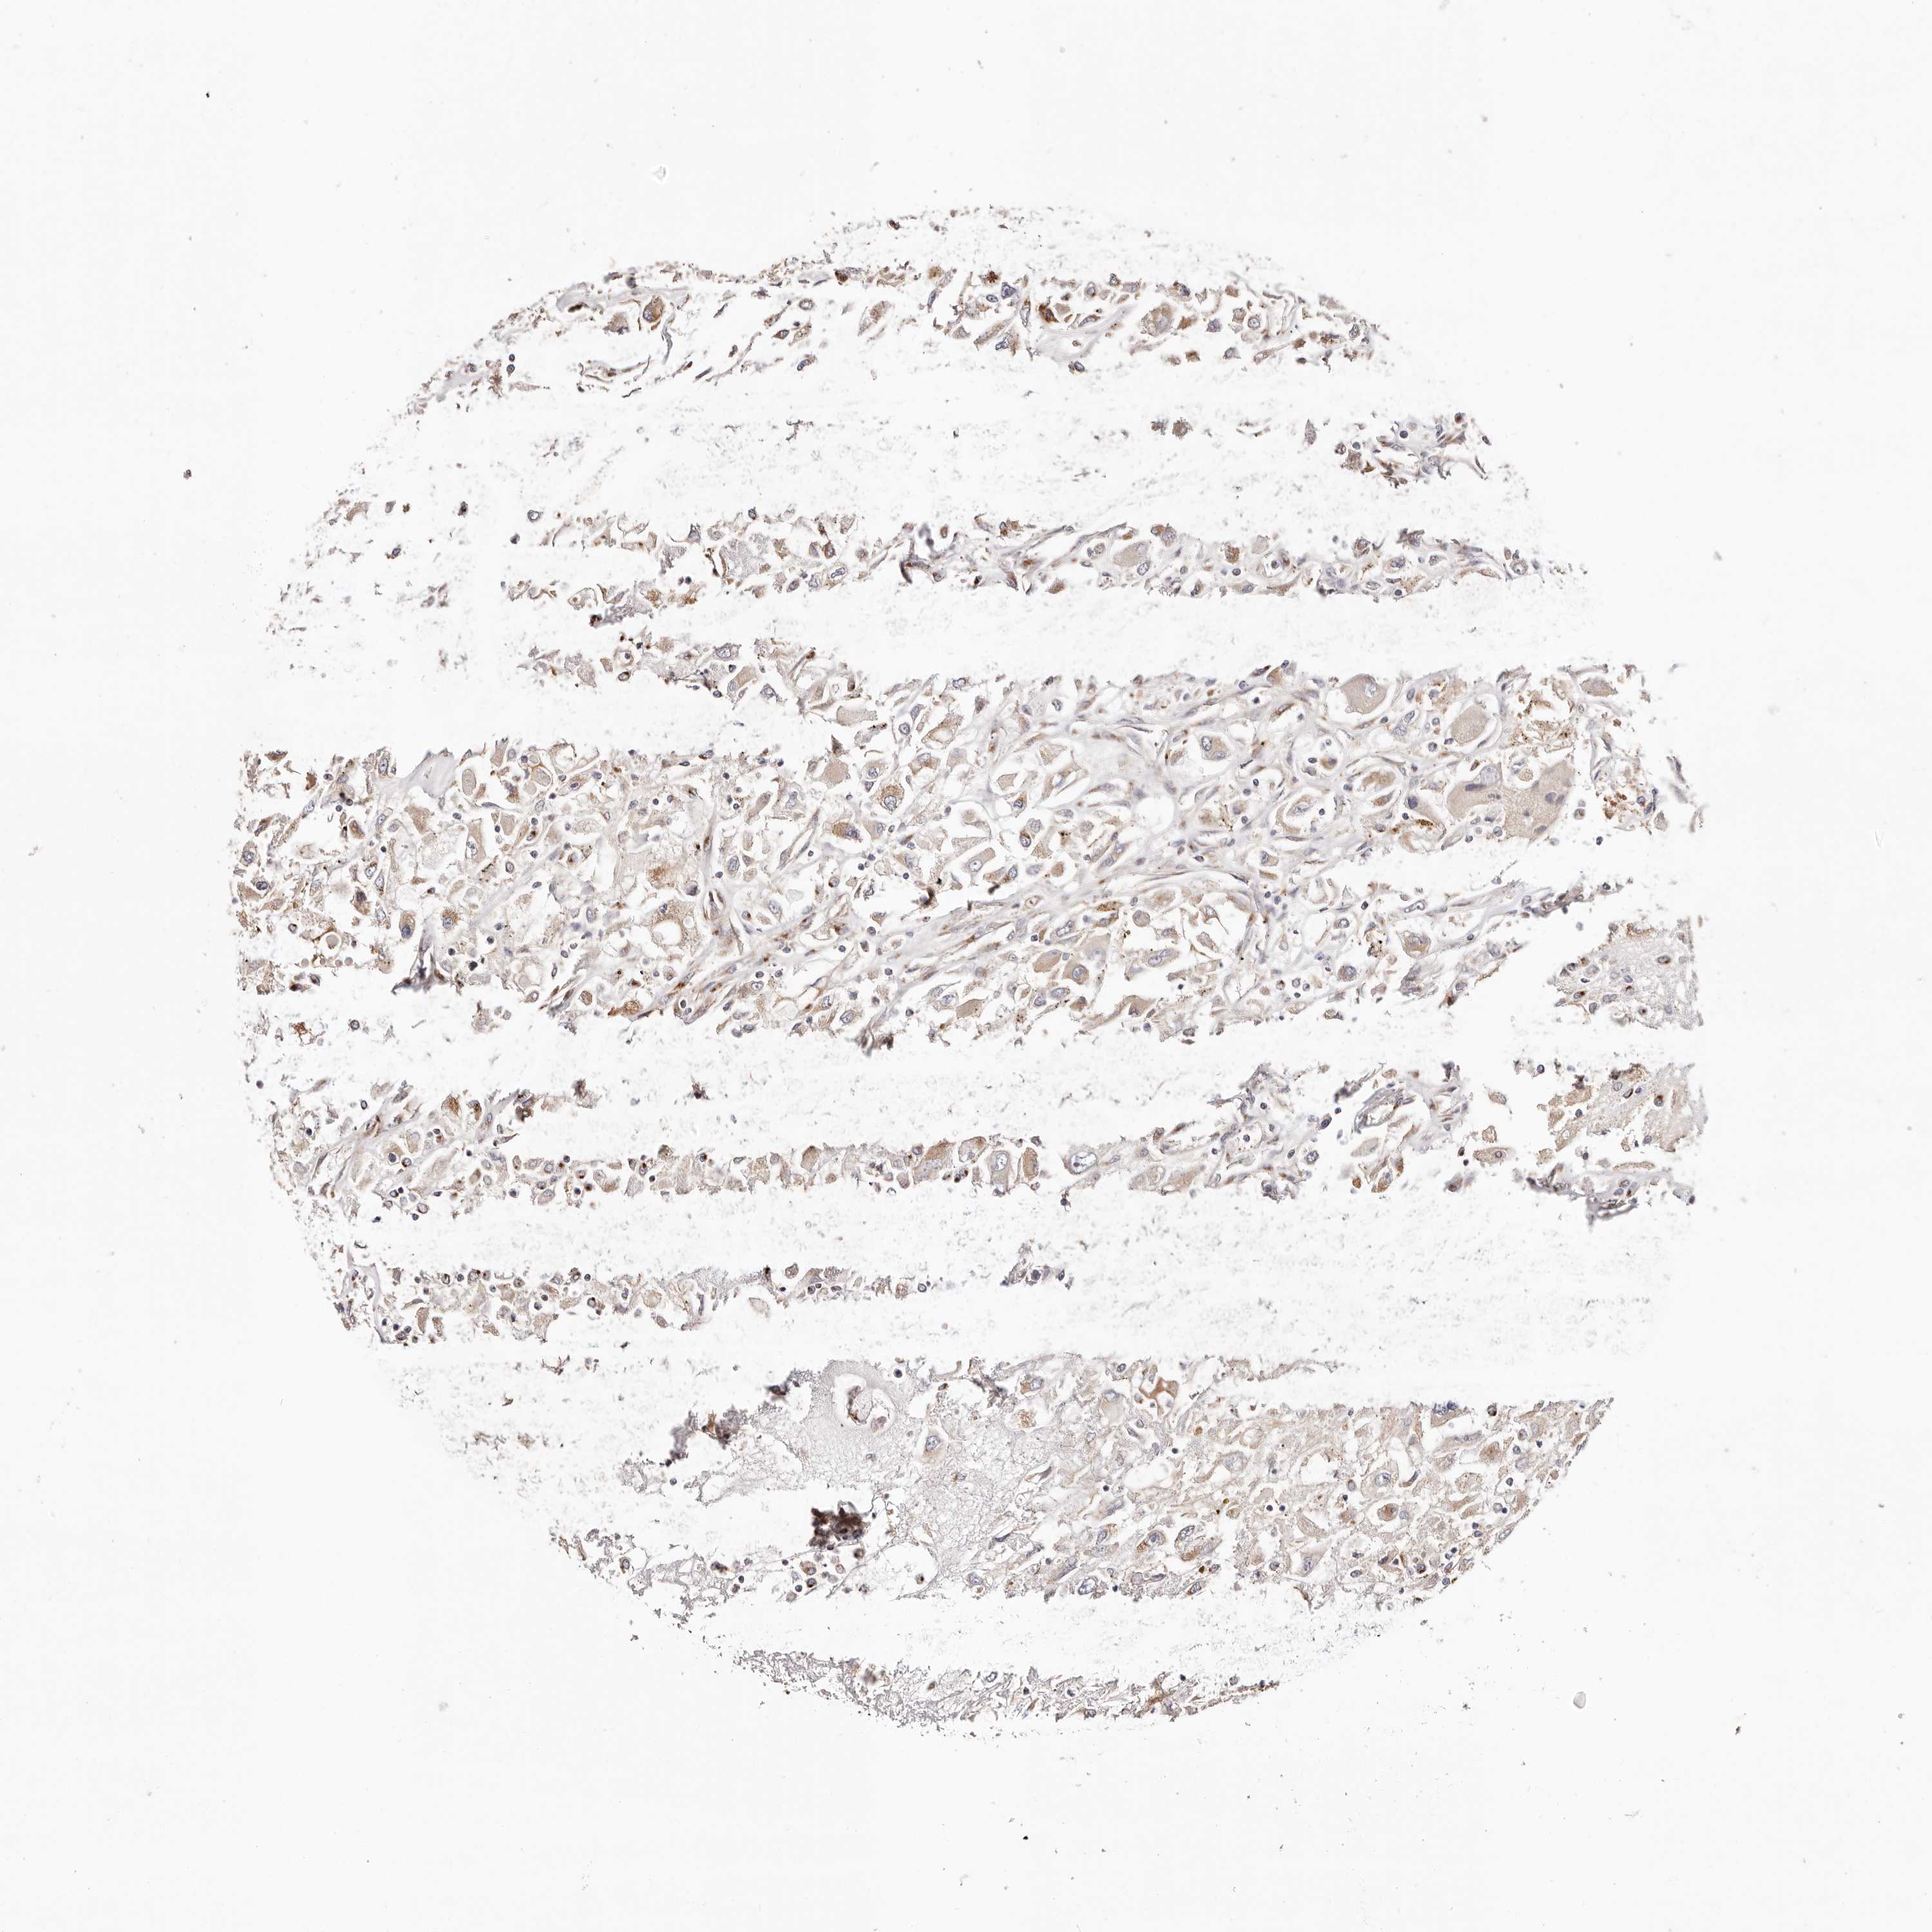

KIDNEY CHROMOPHOBE (TCGA) - Interactive survival scatter ploti

The Survival Scatter plot shows the clinical status (i.e. dead or alive) for all individuals in the patient cohort, based on the same data that underlies the corresponding Kaplan-Meier plots. Patients that are alive at last time for follow-up are shown in blue and patients who have died during the study are shown in red.

The x-axis shows the expression levels (FPKM) of the investigated gene in the tumor tissue at the time of diagnosis. The y-axis shows the follow-up time after diagnosis (years). Both axes are complimented with kernel density curves demonstrating the data density over the axes. The top density plot shows the expression levels (FPKM) distribution among dead (red) and alive patients (blue). The right density plot shows the data density of the survived years of dead patients with high and low expression levels respectively, stratified using the cutoff indicated by the vertical dashed line through the Survival Scatter plot. This cutoff is automatically defined based on the FPKM cutoff that minimizes the p-score. The cutoff can be changed by dragging the vertical line or by entering a cutoff value in the square labeled "Current cut-off".

Under the Survival Scatter plot the p-score landscape (black curve; left axis) is shown together with dead median separation (red curve; right axis). Dead median separation is the difference in median mRNA expression between patients who have died with high and low expression, respectively. It is calculated as follows: median FPKM expression of dead patients with high expression - median FPKM expression of dead patients with low expression. This is intended to aid the user in visually exploring custom cutoffs and the associated p-scores and dead median separation.

Individual patient data is displayed and can be filtered by clicking on one or more of the category buttons on the top of the page. Categories describing expression level and patient information include: high, low, alive, dead, female, male and tumor stages. The scale of the x-axis can be toggled between linear and log-scale by clicking on the "x log" button. Mouse-over function shows TCGA ID, patient information and mRNA expression (FPKM) for each patient.

& Survival analysisi

Kaplan-Meier plots summarize results from analysis of correlation between mRNA expression level and patient survival. Patients were divided based on level of expression into one of the two groups "low" (under cut off) or "high" (over cut off). X-axis shows time for survival (years) and y-axis shows the probability of survival, where 1.0 corresponds to 100 percent.

MAPK6 is not prognostic in Kidney Chromophobe (TCGA)